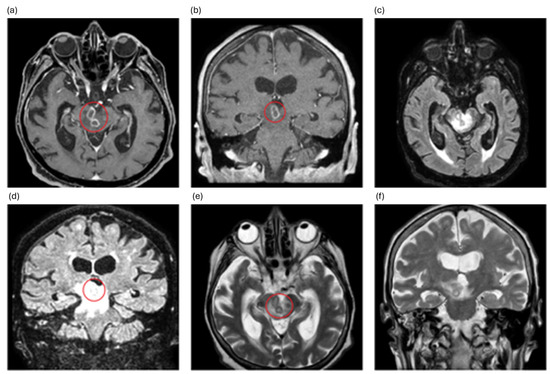

A 30-year-old previously healthy man presented with fever and headache. HIV tests yielded negative results. Cerebrospinal fluid (CSF) analysis revealed pleocytosis (619/µL), elevated protein (210.3 mg/dL) and adenosine deaminase levels, and decreased glucose levels. A positive CSF culture for tuberculosis confirmed the patient [...] Read more.

A 30-year-old previously healthy man presented with fever and headache. HIV tests yielded negative results. Cerebrospinal fluid (CSF) analysis revealed pleocytosis (619/µL), elevated protein (210.3 mg/dL) and adenosine deaminase levels, and decreased glucose levels. A positive CSF culture for tuberculosis confirmed the patient had tuberculous meningitis (TBM). He was treated with methylprednisolone, isoniazid, rifampicin, pyrazinamide, and ethambutol (all highly sensitive). His compliance with medication was good. After six weeks of treatment, he was discharged in stable condition. Eight weeks after onset, he was readmitted with vertigo and right deafness. CSF examination showed worsened pleocytosis (819/µL) and protein levels (4296.1 mg/dL). Contrast-enhanced MRI revealed enhancement of meninges in the brainstem and spinal cord as well as the right vestibulocochlear nerve. No brain abscesses were observed. Based on these findings, a paradoxical reaction (PR) with vestibulocochlear neuritis following antituberculous therapy initiation was suspected. He received oral prednisolone, leading to rapid resolution of vestibulocochlear symptoms within two days. Although cranial nerve enhancement due to PR has been mentioned in the literature, specific imaging demonstrating it is scarce. This case highlights PR as a cause of cranial neuropathy in TBM and provides clear radiological evidence of direct inflammatory spread to the vestibulocochlear nerve, bridging a gap in the current literature. Full article

Show Figures

Figure 1